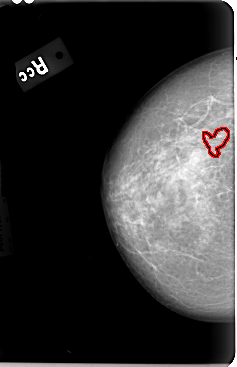

B_3030_1.LEFT_CC

FILE: B_3030_1.LEFT_CC.OVERLAY

TOTAL_ABNORMALITIES 1

ABNORMALITY 1

LESION_TYPE CALCIFICATION TYPE PUNCTATE DISTRIBUTION SEGMENTAL

ASSESSMENT 4

SUBTLETY 2

PATHOLOGY MALIGNANT

TOTAL_OUTLINES 4

BOUNDARY

CORE